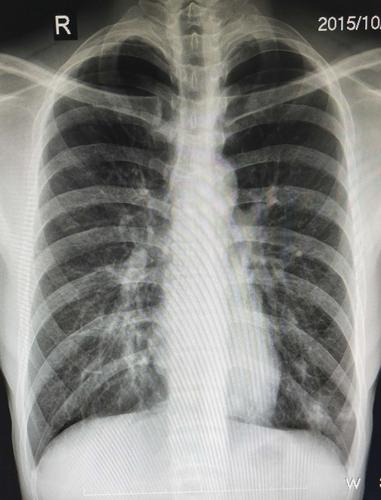

图为患有潜在大叶性肺炎患者的胸部x光片

肺炎病人的胸部x光片